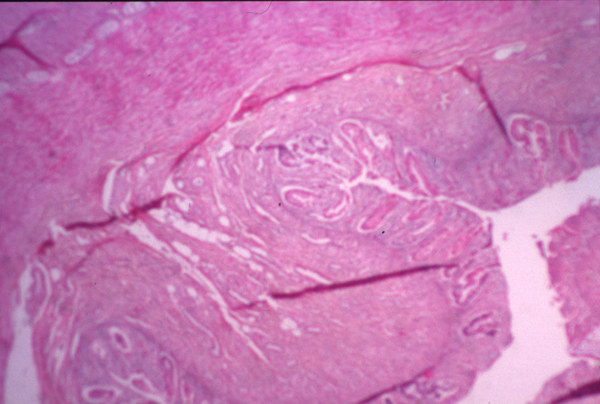

010